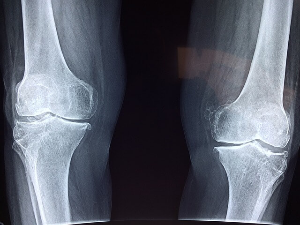

검사

이중 에너지 x선 흡수 측정법으로 골다공증을 진단하는데 사용되는 가장 일반적인 검사로 척추, 고관절 및 기타 부위의 골밀도를 측정하는 무통 비침습 검사입니다. 또는 정량적 컴퓨터단층촬영법으로 척추와 엉덩이의 골밀도를 측정하는 영상검사이며 뼈의 3D 이미지를 만들기 위해 특별한 종류의 CT 스캐너를 사용합니다. 이중 에너지 X선 흡수 측정법보다 덜 사용되지만 비만이나 조금 다른 조건을 가진 사람들에게 더 정확한 검사이기도 합니다. 그리고 초음파검사법으로 음파를 이용하여 발뒤꿈치나 정강이뼈의 골밀도를 측정하는 비침습적 검사로 다른 검사들보다 정확도는 떨어지지만 선별 도구로 사용하거나 시간 경과에 따른 골밀도의 변화를 모니터링하는데 사용합니다. 그 외 혈액 및 소변검사로 골밀도나 콜라겐과 같은 뼈 회전의 특정 마커 수준을 측정하는데 사용되며 뼈 형성 및 파괴 속도에 대한 정보를 제공할 수 있습니다. 나이, 성별, 체중 및 가족력과 같은 다른 요소를 사용하여 사람의 골절 위험을 평가할 수도 있고 여러 도구를 사용하여 이러한 요인을 기반으로 10년간 골절 위험을 추정하기도 합니다. 모든 사람이 골다공증 검사를 받을 필요는 없으며 일반적으로 65세 이상의 폐경 후 여성, 70세 이상의 남성 및 골절 병력, 저체중 또는 특정 의학적 조건과 같은 골다공증의 위험이 있는 젊은 사람들에게 검사를 권장합니다. 골다공증의 위험이 걱정된다면 검사가 나에게 적합한지에 대해 전문의와 상담해 보시기 바랍니다.